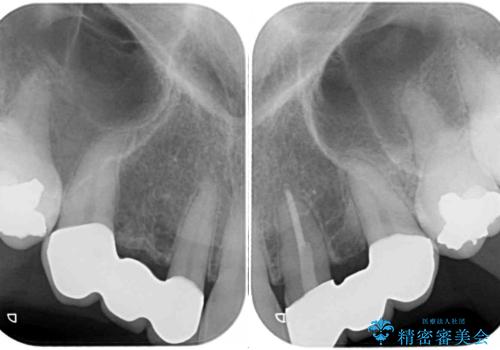

上顎は左右ともに小臼歯が欠損しており、右側は乳前歯が残っている状態でした。

ブリッジによる補綴治療にて、欠損や隙間を補完することとしましたが、神経を取り除いたり、審美的に不自然になることを避けるため、部分矯正を併用することとしました。

乳歯は事前に抜歯することとしました。